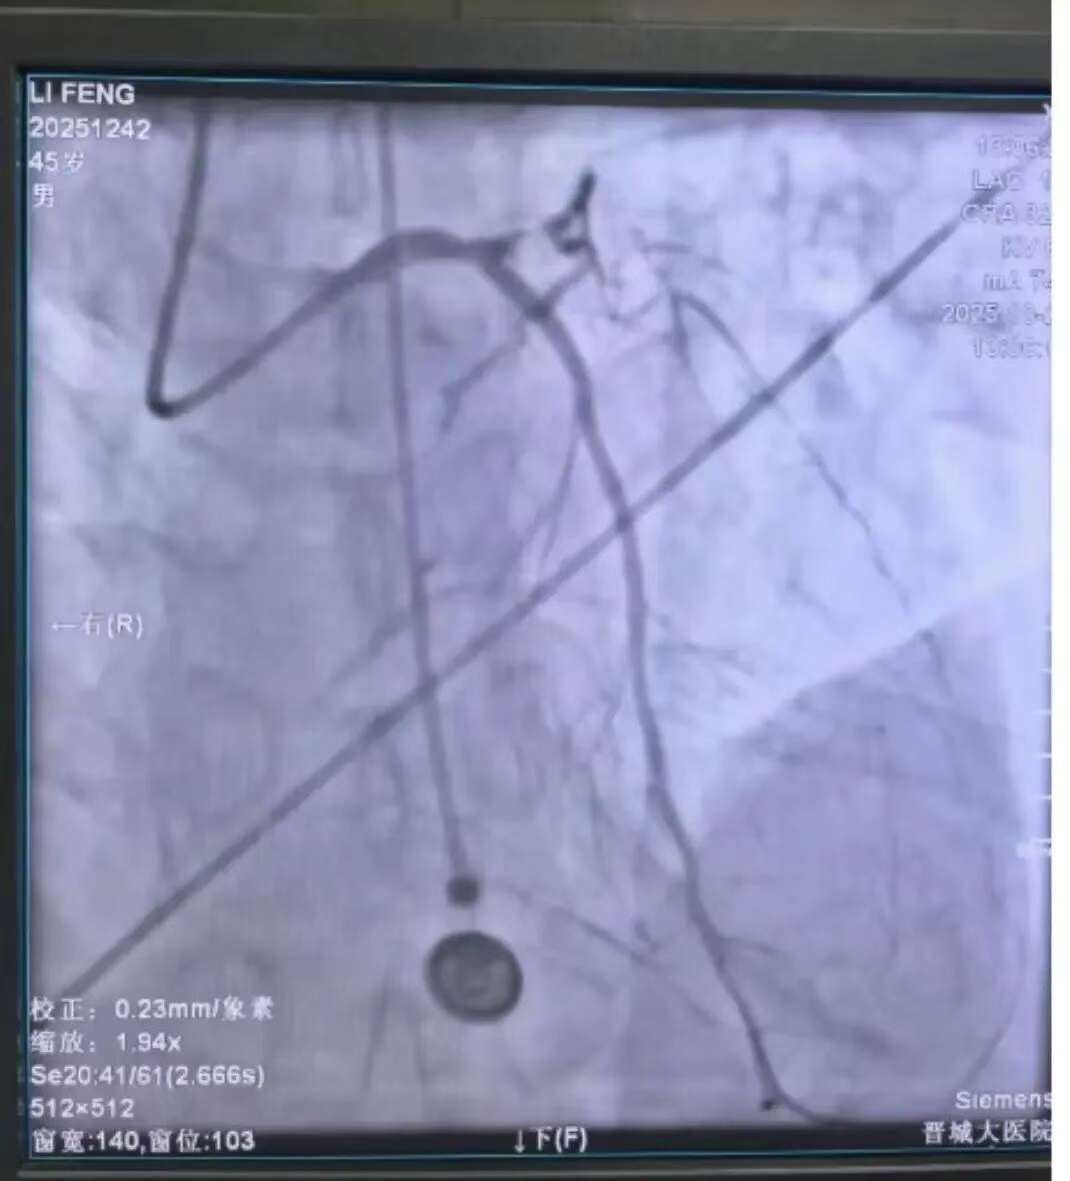

导管室手术团队立即集合,主动脉内球囊反搏(IABP)设备迅速就位,ECMO体外生命支持系统全程待命。患者抵达医院后,直接由救护车经绿色通道直送导管室,只为在最短时间内为患者争取生机。

毋会芃副院长、崔少波院长助理带队,介入团队迅速为患者实施急诊冠脉介入治疗。手术精准指向本次心梗相关血管前降支,短短数分钟血管就被开通,并植入支架一枚,前向血流TIMI3级;同时在严重影响血流的回旋支近段置入支架一枚。